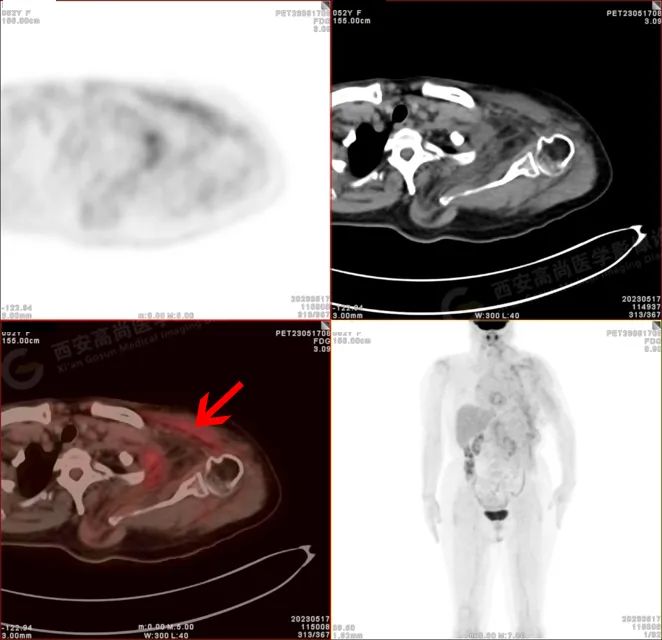

PET/CT 影像图

检查所见

左侧上臂、颈 4-腰 4 椎体水平左侧颈、左侧肩部、左侧腋窝、左侧胸部(含左侧乳腺)、左侧腹部、左侧背部广泛区域皮下及肌肉区可见疏松、肿胀混杂密度软组织病变,边界模糊不清,相邻骨质结构完整,上述病变呈不均匀放射性摄取轻度异常增高,SUV 最大值介于 1.2-2.4。上述改变,符合韧带样纤维瘤病。